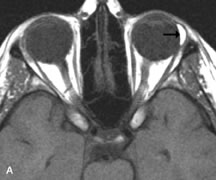

Lymphomas have MRI characteristics similar to those of inflammatory lesions in that they are hypointense to fat and isointense to muscle on T1-weighted images (Fig. 22). They may appear hyperintense to fat on T2-weighted images, perhaps owing to less fibrosis than that seen in orbital inflammatory pseudotumor, although this is not a consistent finding.31,50,66 Lymphoid tumors typically enhance moderately after contrast injection. Unfortunately, studies have shown that tumor density and homogeneity are similar between inflammatory and malignant orbital infiltrates, and MRI cannot differentiate these lesions.72,73

Fig. 22. A and B. T1- and (C) T2-weighted MR scans demonstrate a poorly defined multicompartmental mass enveloping the lateral rectus, superior rectus, and levator palpebrac superioris muscles. The lesion is isointense to brain on T1- and T2-weighted scans, as is typical for highly cellular neoplasms. D. Postcontrast fat-suppressed T1-weighted scan demonstrates intense enhancement of the infiltrating intraconal and extraconal tumor.